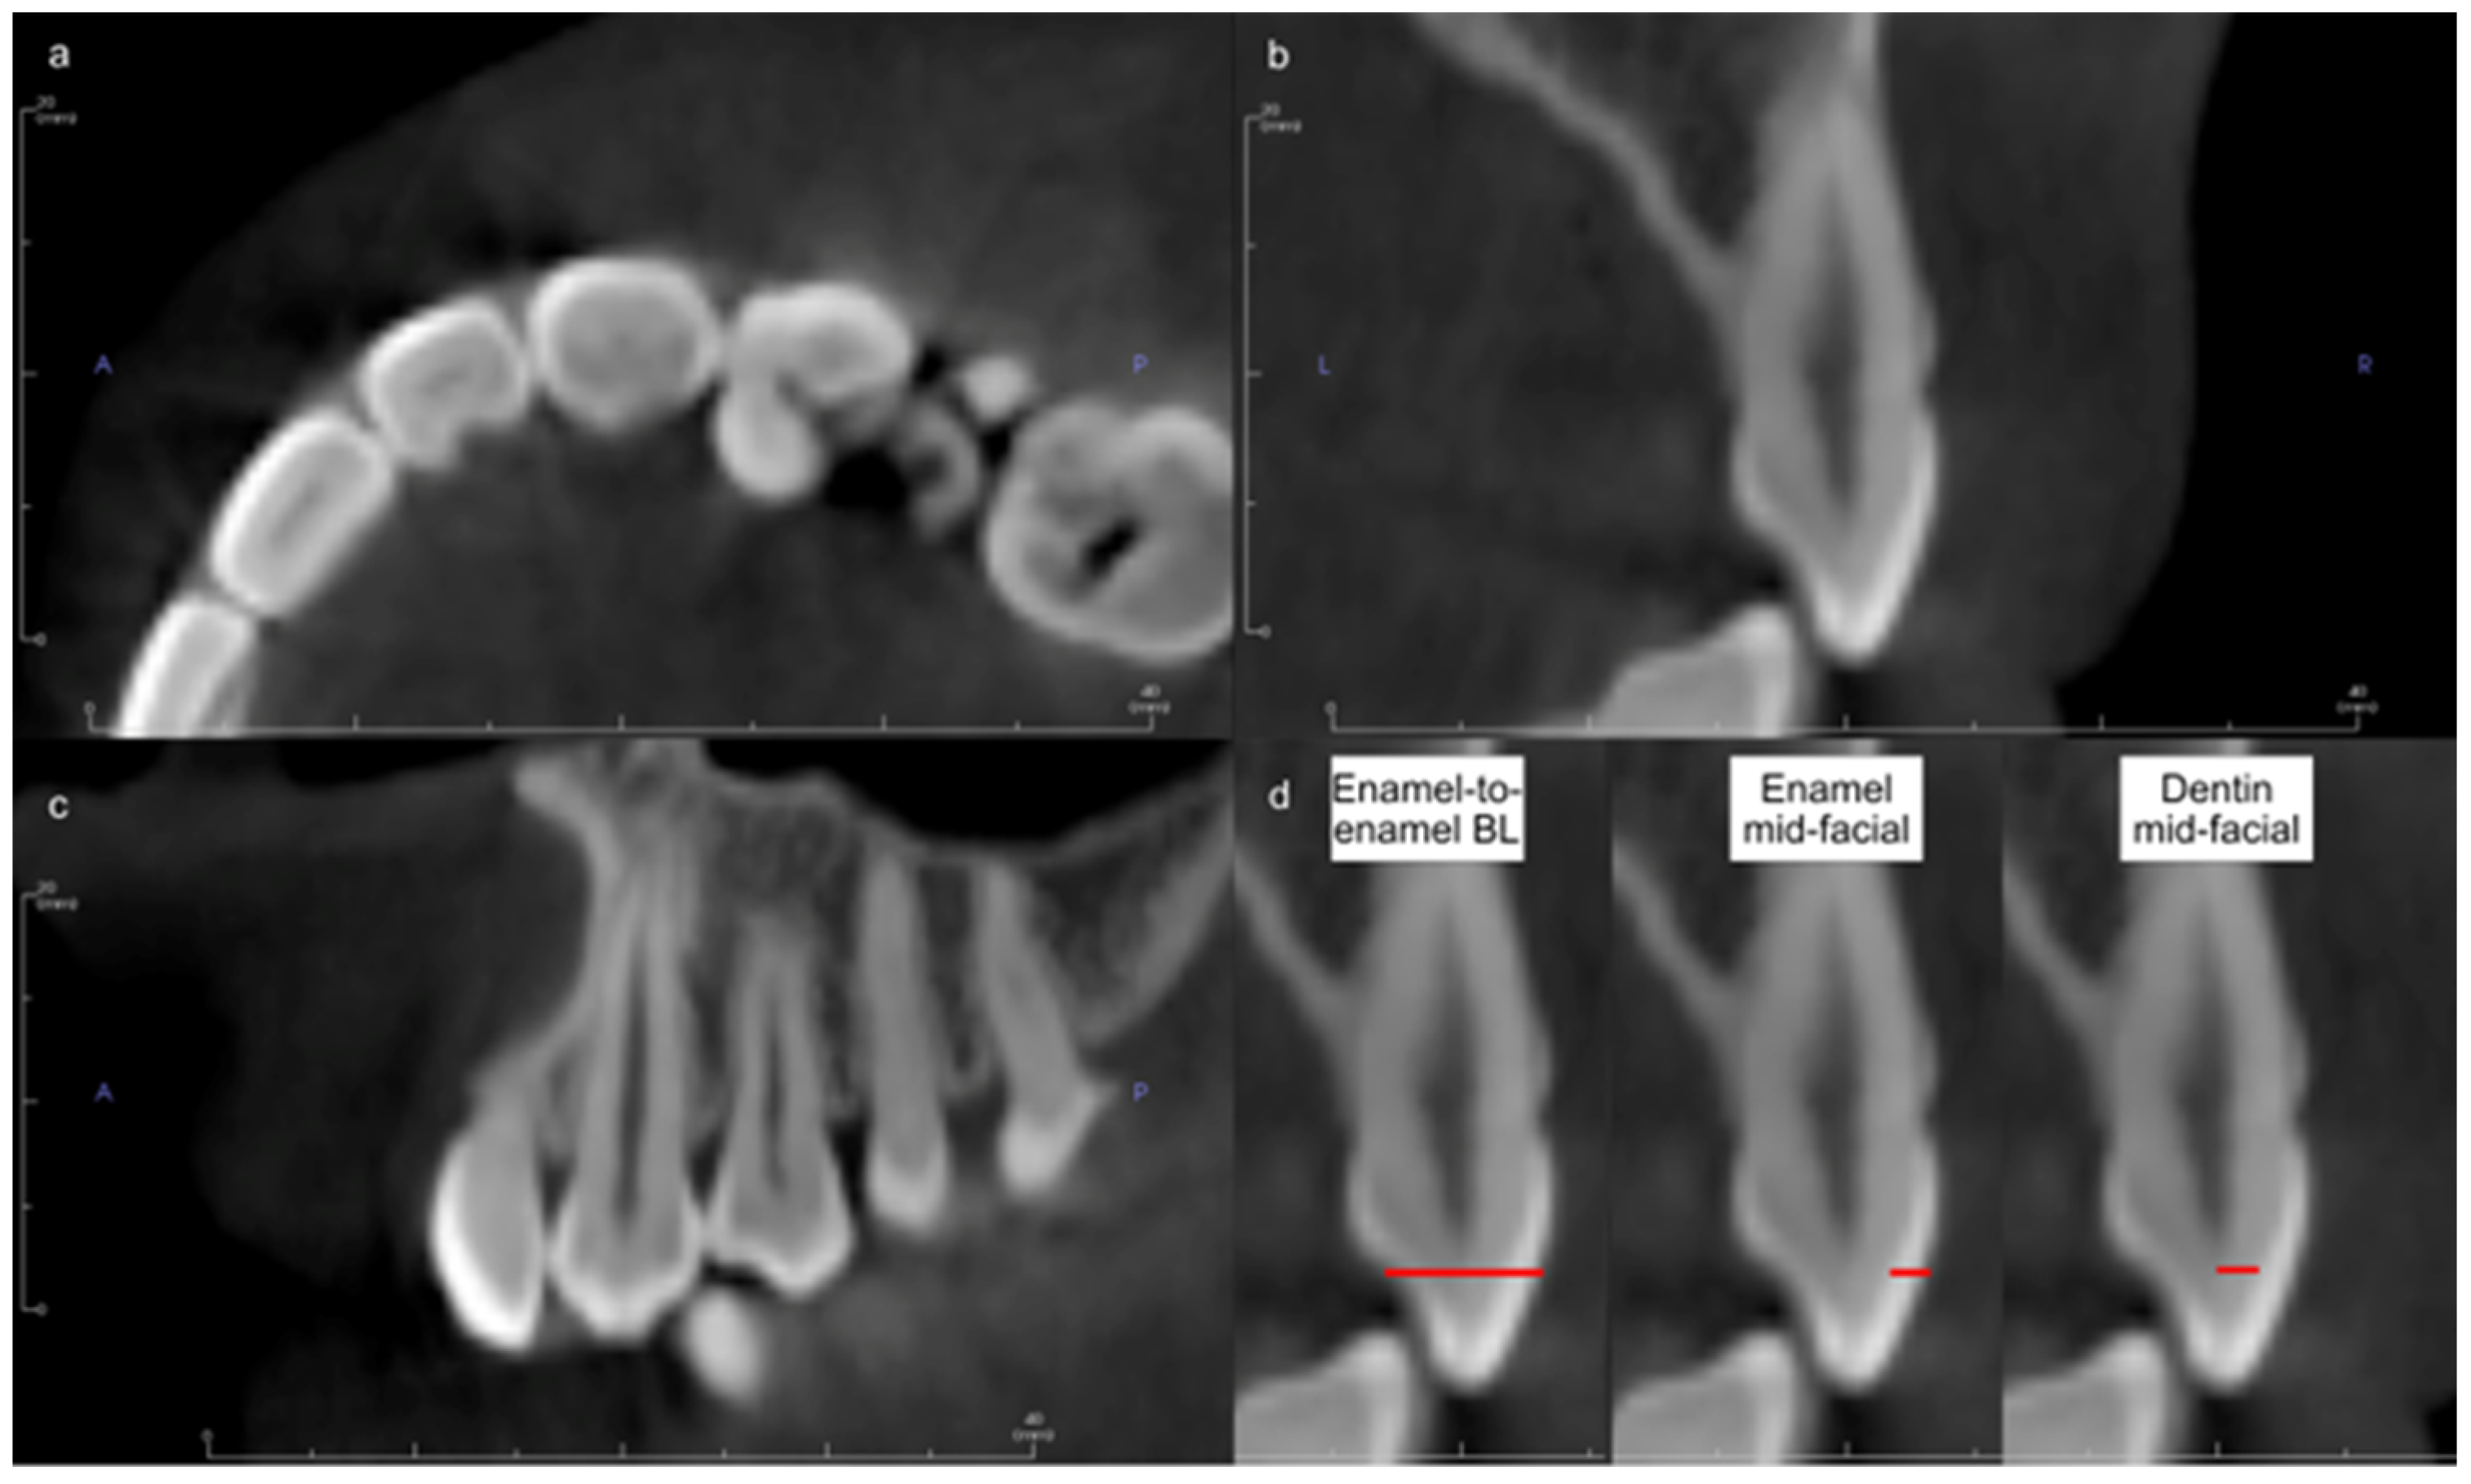

| Thickness | Overall | Control | Case |

|---|---|---|---|

| Mean ± SD | Mean ± SD | Mean ± SD | |

| Enamel-to-enamel buccolingual | 5.97 ± 1.91 | 5.89 ± 1.89 | 6.08 ± 1.94 |

| Enamel mid-facial | 1.24 ± 0.19 | 1.24 ± 0.19 | 1.24 ± 0.22 |

| Dentin mid-facial | 1.87 ± 0.84 | 1.85 ± 0.84 | 1.89 ± 0.84 |